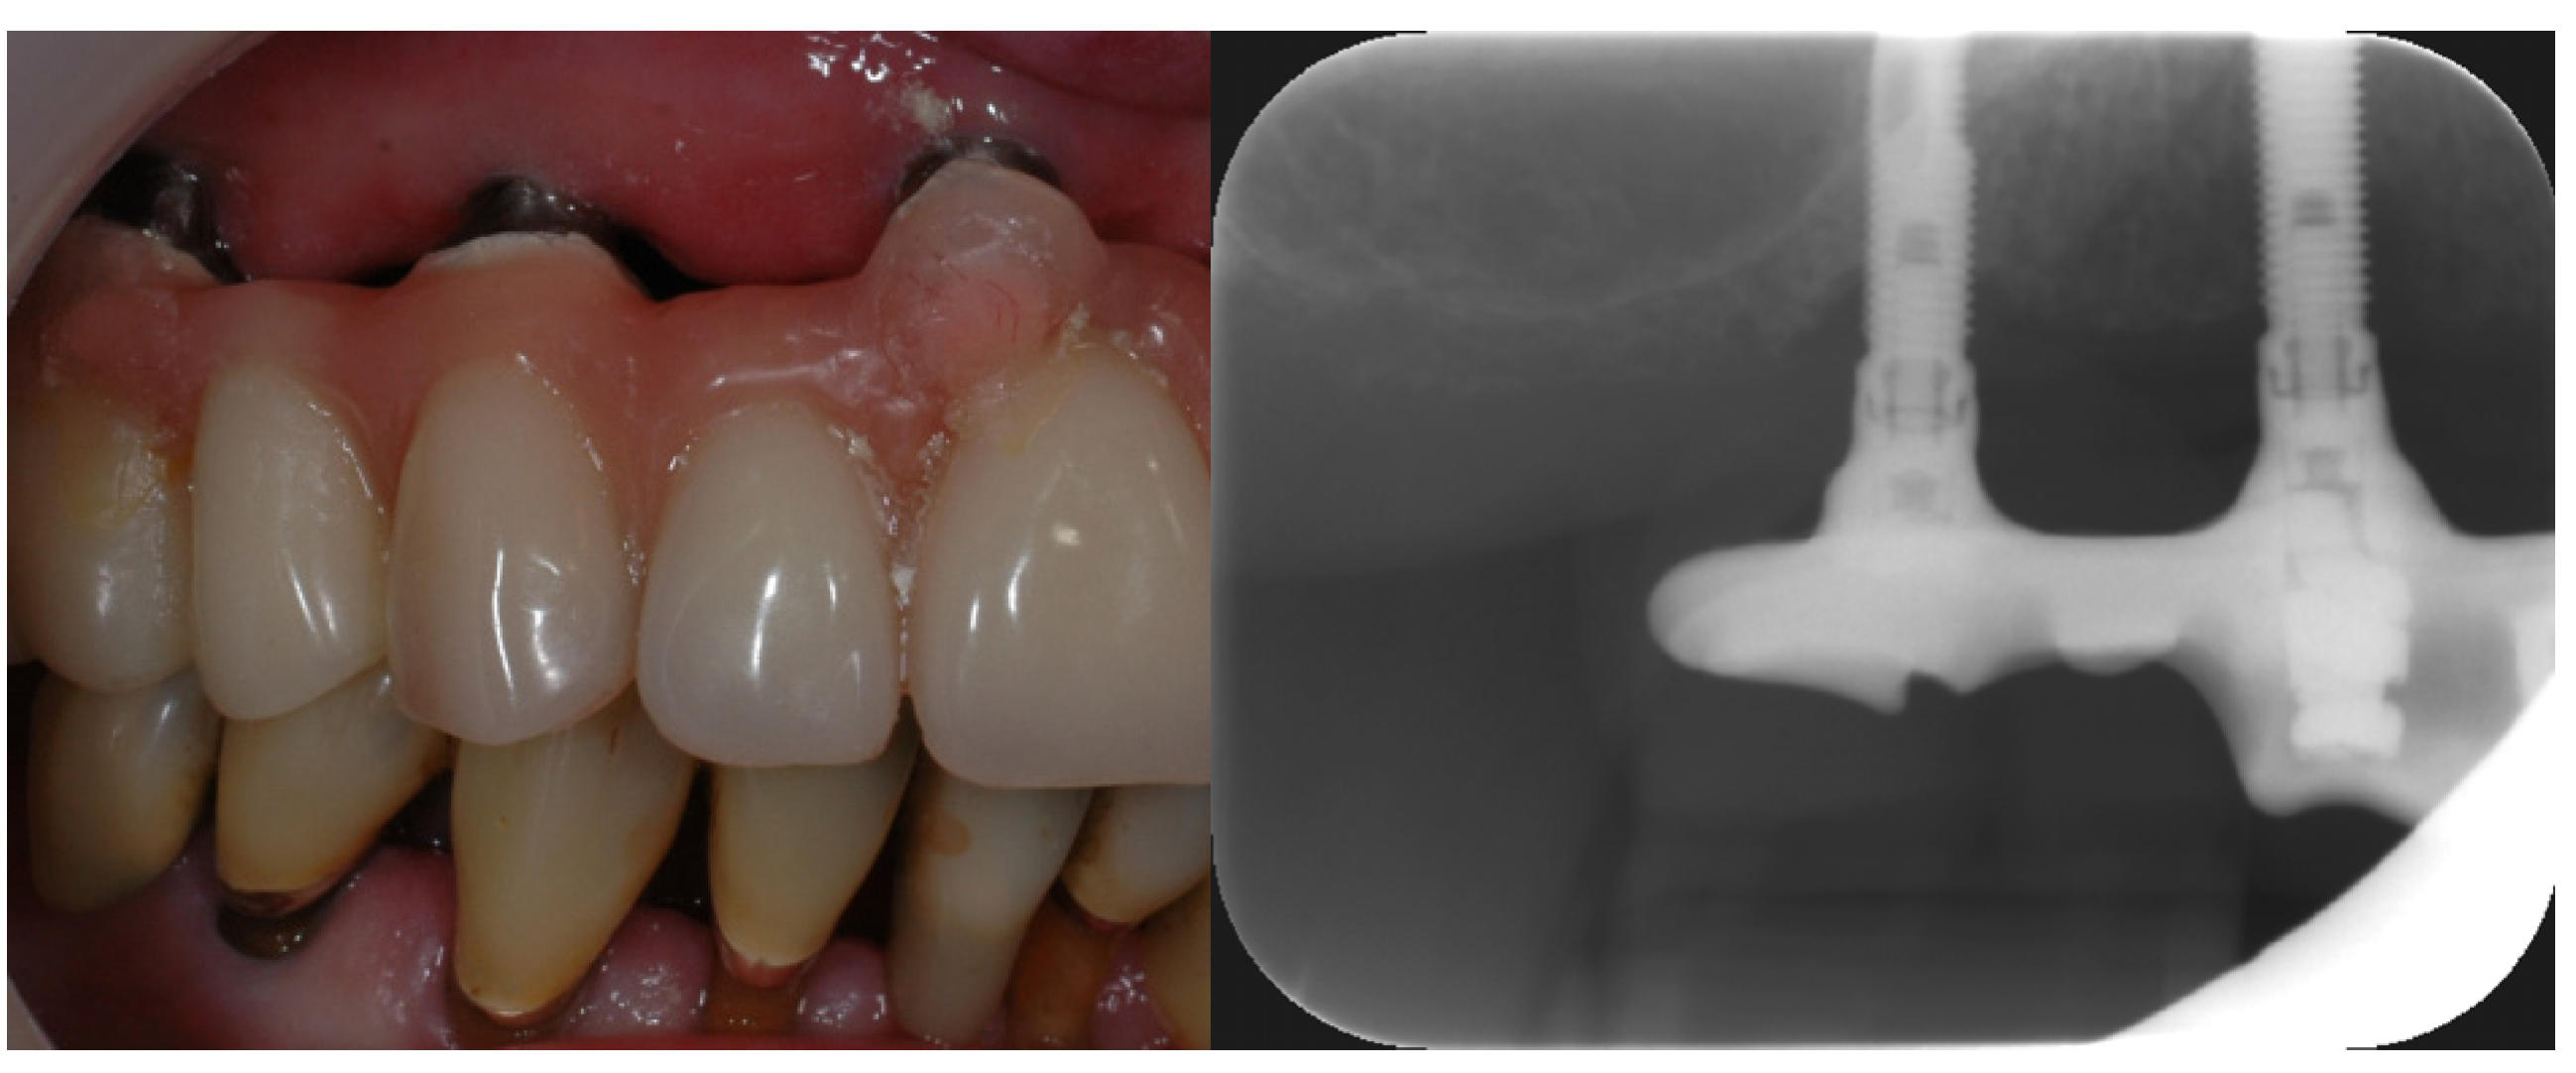

Dental implants are most commonly made of titanium which are inserted into the alveolar bone to function as artificial roots [35]. They penetrate the oral mucosa and are therefore exposed to the oral microflora. Implants usually have a smooth polished surface in the areas that are exposed to the oral cavity which can be easily cleaned. They are, however, often made of several small components that are fixed together with tiny screws [44]. There will always be gaps and crevices between these parts, creating almost a “greenhouse” for bacterial growth. Pathogenic bacteria in such gaps can cause inflammation in the surrounding bone or inhibit osseointegration [25,35]. Modern implants have a very rough surface in the part that is to be osseointegrated in the alveolar bone to enhance early bone attachment [35]. If the bone reacts inadequately or does not grow to cover the rough area, this will be exposed to the oral cavity as well. This surface will easily be colonized by oral bacteria which then will be almost impossible to remove completely (Figure 6). If pathogenic organisms are allowed to settle in such an area, it will be extremely difficult to arrest inflammation (periimplantitis). Since the implant is in direct contact with bone, the inflammation will potentially be able to spread via the bone or the blood faster than similar inflammation around teeth [16,35]. The teeth are separated from the alveolar bone by fibrous tissue, which work as a barrier to bacterial ingrowth. Currently, research cannot fully explain the differences between periimplantitis and periodontitis [45]. The microorganisms surrounding an implant with healthy supporting tissues are similar to those surrounding a healthy tooth [46]. However, periimplantitis locations seem to have more bacterial species and fungal species than locations associated with periodontitis. This is possibly an effect of the titanium in the implant.

Figure 6. Implant in the upper jaw supporting a fixed denture. The rough area on the molar region implant is exposed due to previous periimplantitis (photo: Marit Øilo).